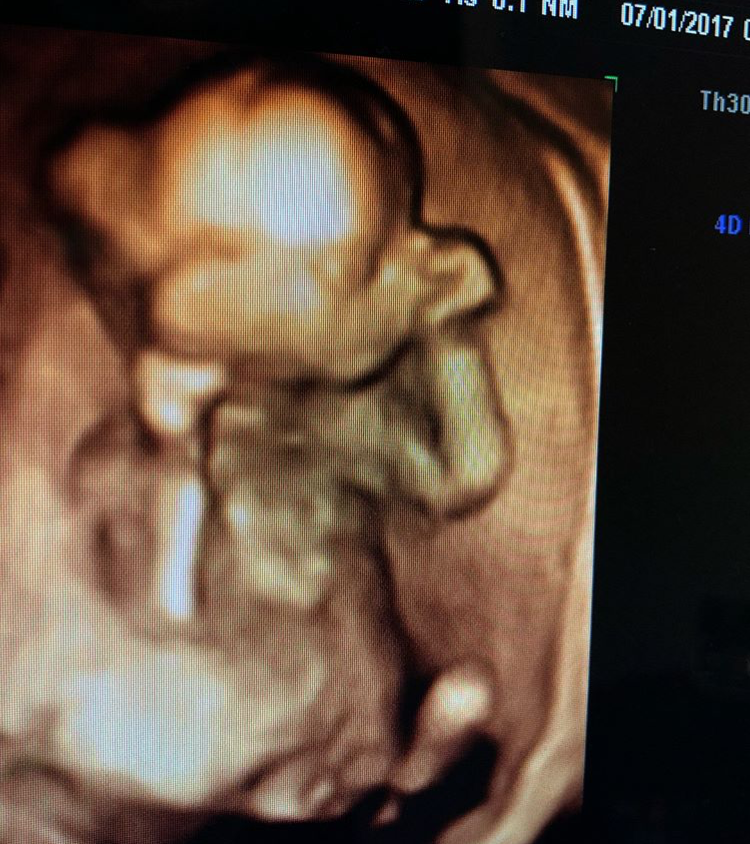

3 Aylık 13 günlük gebesiniz. Bebeğin boyu 7 cm kilosu ise 25 gram civarındadır. Haftaları beklemek daha doğru olacaktır. 13 haftalık bebek ultrason görüntüsü artık bebeğinizi oldukça iyice seçebildiğiniz bir fotoğraf gibidir. 13 haftalık gebelikte karın büyüklüğü artar karnı belirginleşir eskiden giydikleri kıyafetlere artık sığamayabilir.

13 haftalık gebelik hamilelik görüntüsü. 13 haftalık bebek ultrason görüntüsü artık bebeğinizi oldukça iyice seçebildiğiniz bir fotoğraf gibidir. Haftaları beklemek daha doğru olacaktır. Haftalık gebelik cinsiyet görüntüsü bazı durumlarda bebeğin pozisyonu uygun ise hekim tarafından yakalanabilmektedir. 13 haftalık bebeğin ultrason görüntüsü.

13 haftalık bebek görüntüsü anne adaylarının heyecanla beklediği ultrason kontrolleriyle takip edilir. 13 haftalık bebek görüntüsü anne adaylarının heyecanla beklediği ultrason kontrolleriyle takip edilir. Bebek erkek ise testisleri oluşmuştur ve penisi büyümeye başlar. Bebeğiniz artık giderek minik bir insan görüntüsü alıyor. Haftadan itibaren tahmin edilmeye başlanır ancak kesin olarak bilmek için 20.

13 haftalık hamile olan anne adaylarının çok fazla merak ettiği bir diğer konu ise bu haftada bebeğin cinsiyetini öğrenme şansının bulunup bulunmadığıdır. 13 haftalık bebeğin ultrason görüntüsünde bebeğin hareketleri de izlenebilir. Erkek bebeklerde mide bulantısı gibi semptomlar pek görülmez. 13 HAFTALIK GEBELİK HAMİLELİK GÖRÜNTÜSÜ. Bu bağlamda 13 haftalık bebek görüntüsü cinsiyeti incelendiğinde bazı ipuçlarını tıbbi açıdan görebilmekteyiz.

13 haftalık bebeğin ultrason görüntüsü. Bu bağlamda 13 haftalık bebek görüntüsü cinsiyeti incelendiğinde bazı ipuçlarını tıbbi açıdan görebilmekteyiz. Hamilelik haftası 120 - 126. Erkek bebeklerde mide bulantısı gibi semptomlar pek görülmez. 3 Aylık 13 günlük gebesiniz.